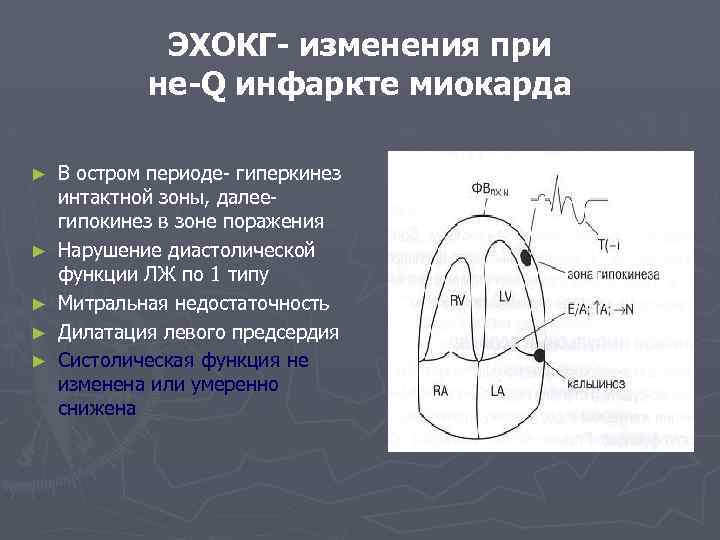

ЭХОКГ- изменения при не-Q инфаркте миокарда ► ► ► В остром периоде- гиперкинез интактной зоны, далеегипокинез в зоне поражения Нарушение диастолической функции ЛЖ по 1 типу Митральная недостаточность Дилатация левого предсердия Систолическая функция не изменена или умеренно снижена